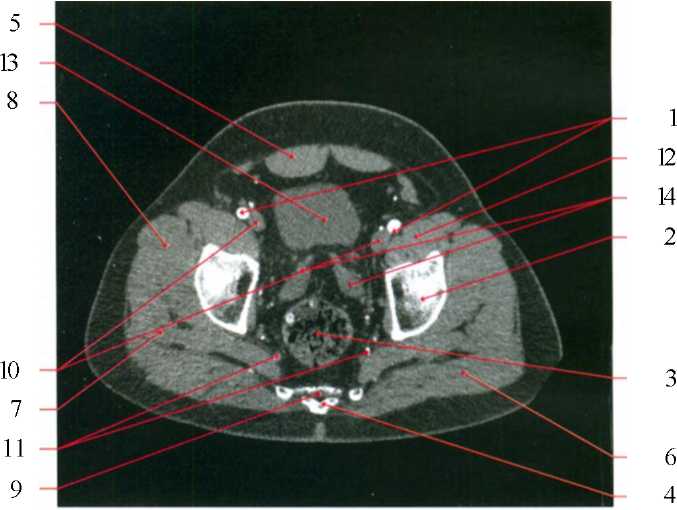

1) общие подвздошные артерии; 2) крыло подвздошной кости; 3) восходящая ободочная кишка; 4) поясничный позвонок; 5) прямая мышца живота; 6) позвоночные мышцы; 7) длинная мышца спины; 8) позвоночный канал; 9) бифуркация нижней полой вены; 10) тонкий кишечник; 11) большая поясничная мышца; 12) наружная косая мышца; 13) внутренняя косая мышца.

I) наружные подвздошные артерии; 2) крыло подвздошной кости; 3) слепая кишка; 4) крестец; 5) прямая мышца живота; 6) большая ягодичная мышца; 7) средняя ягодичная мышца; 8) малая ягодичная мышца; 9) сакральный канал; 10) наружная подвздошная вена; II) внутренняя подвздошная вена; 12) внутренние подвздошные артерии; 13) подвздошно-поясничная мышца.